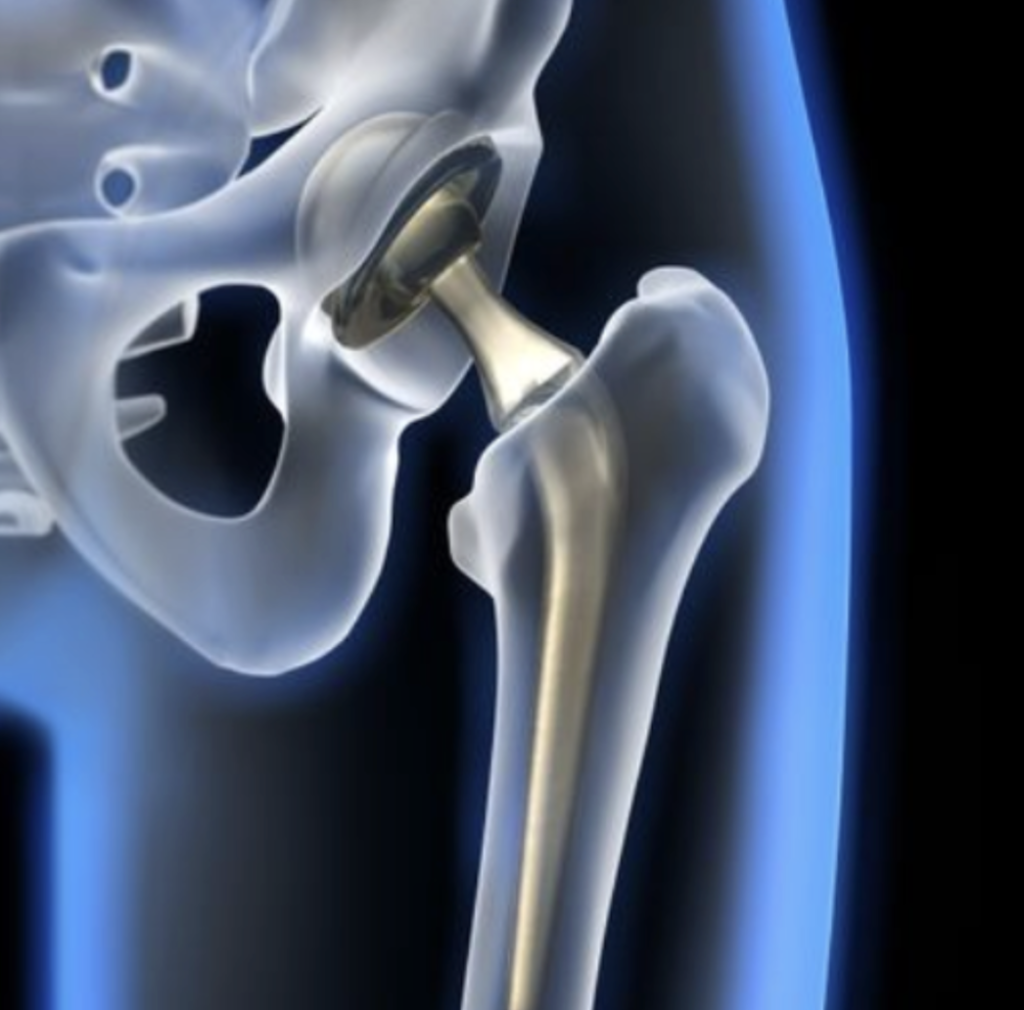

La prothèse de hanche est une intervention chirurgicale couramment pratiquée par le Dr Gastaud pour remplacer une articulation de la hanche endommagée ou usée. Cette procédure est généralement recommandée pour les personnes souffrant d’arthrose, d’arthrite rhumatoïde, de nécrose de la tête fémorale ou de fractures graves de la hanche.

Qu’est-ce que c’est ?

La prothèse de hanche consiste en la mise en place de composants artificiels qui reconstituent l’articulation de la hanche. Elle vise à réduire la douleur, améliorer la mobilité et augmenter la qualité de vie des patients.